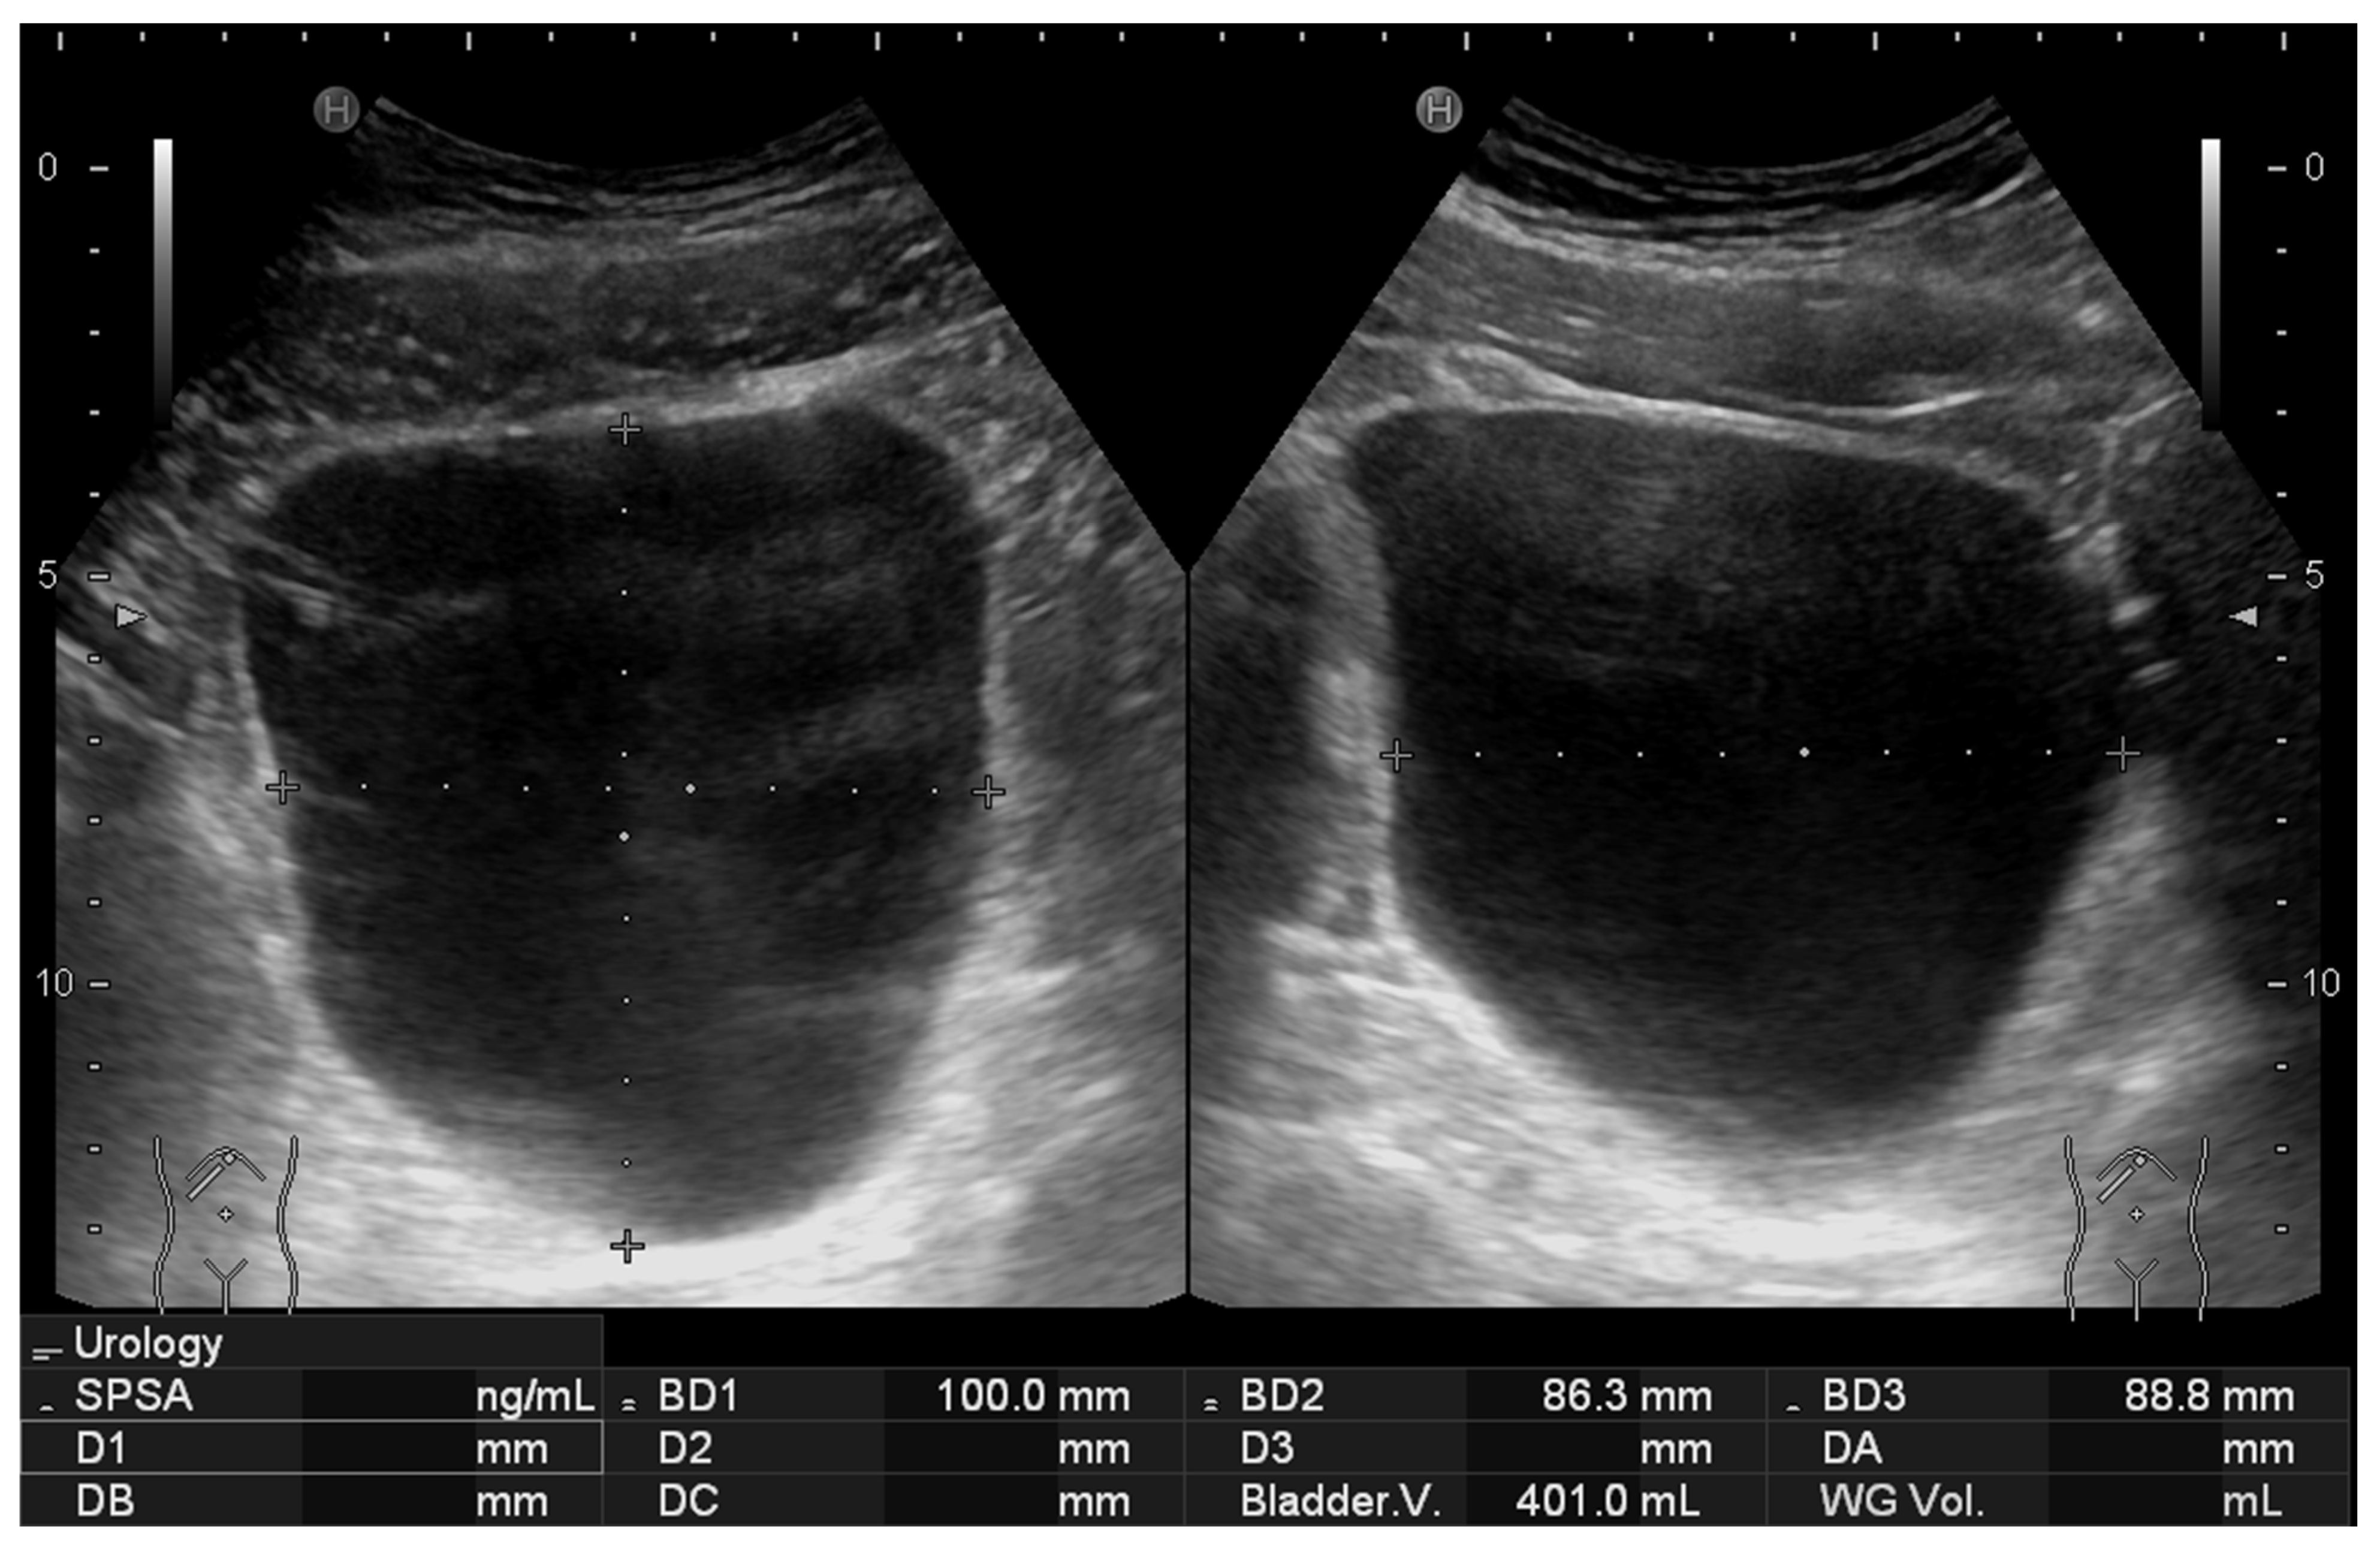

Figure 4. Representative 2D ultrasound image obtained using the standard method, showing the volume estimation at the bottom based on manual caliper measurements.

The study compared two sonographic methods for bladder volume estimation accuracy and agreement. The first method (2D method) employed traditional 2D bladder volume measurement by calculating height, width, and depth dimensions using the HI VISION Avius ultrasound system (Hitachi Medical Corporation, Tokyo, Japan) equipped with an EUP-C715 Abdominal Convex transducer operating at 1–5 MHz frequency range. This device automatically calculates bladder volume using the built-in calculation tool that assumes a spheroidal shape according to the formula:

V o l u m e = π 6 h e i g h t × w i d t h   × d e p t h